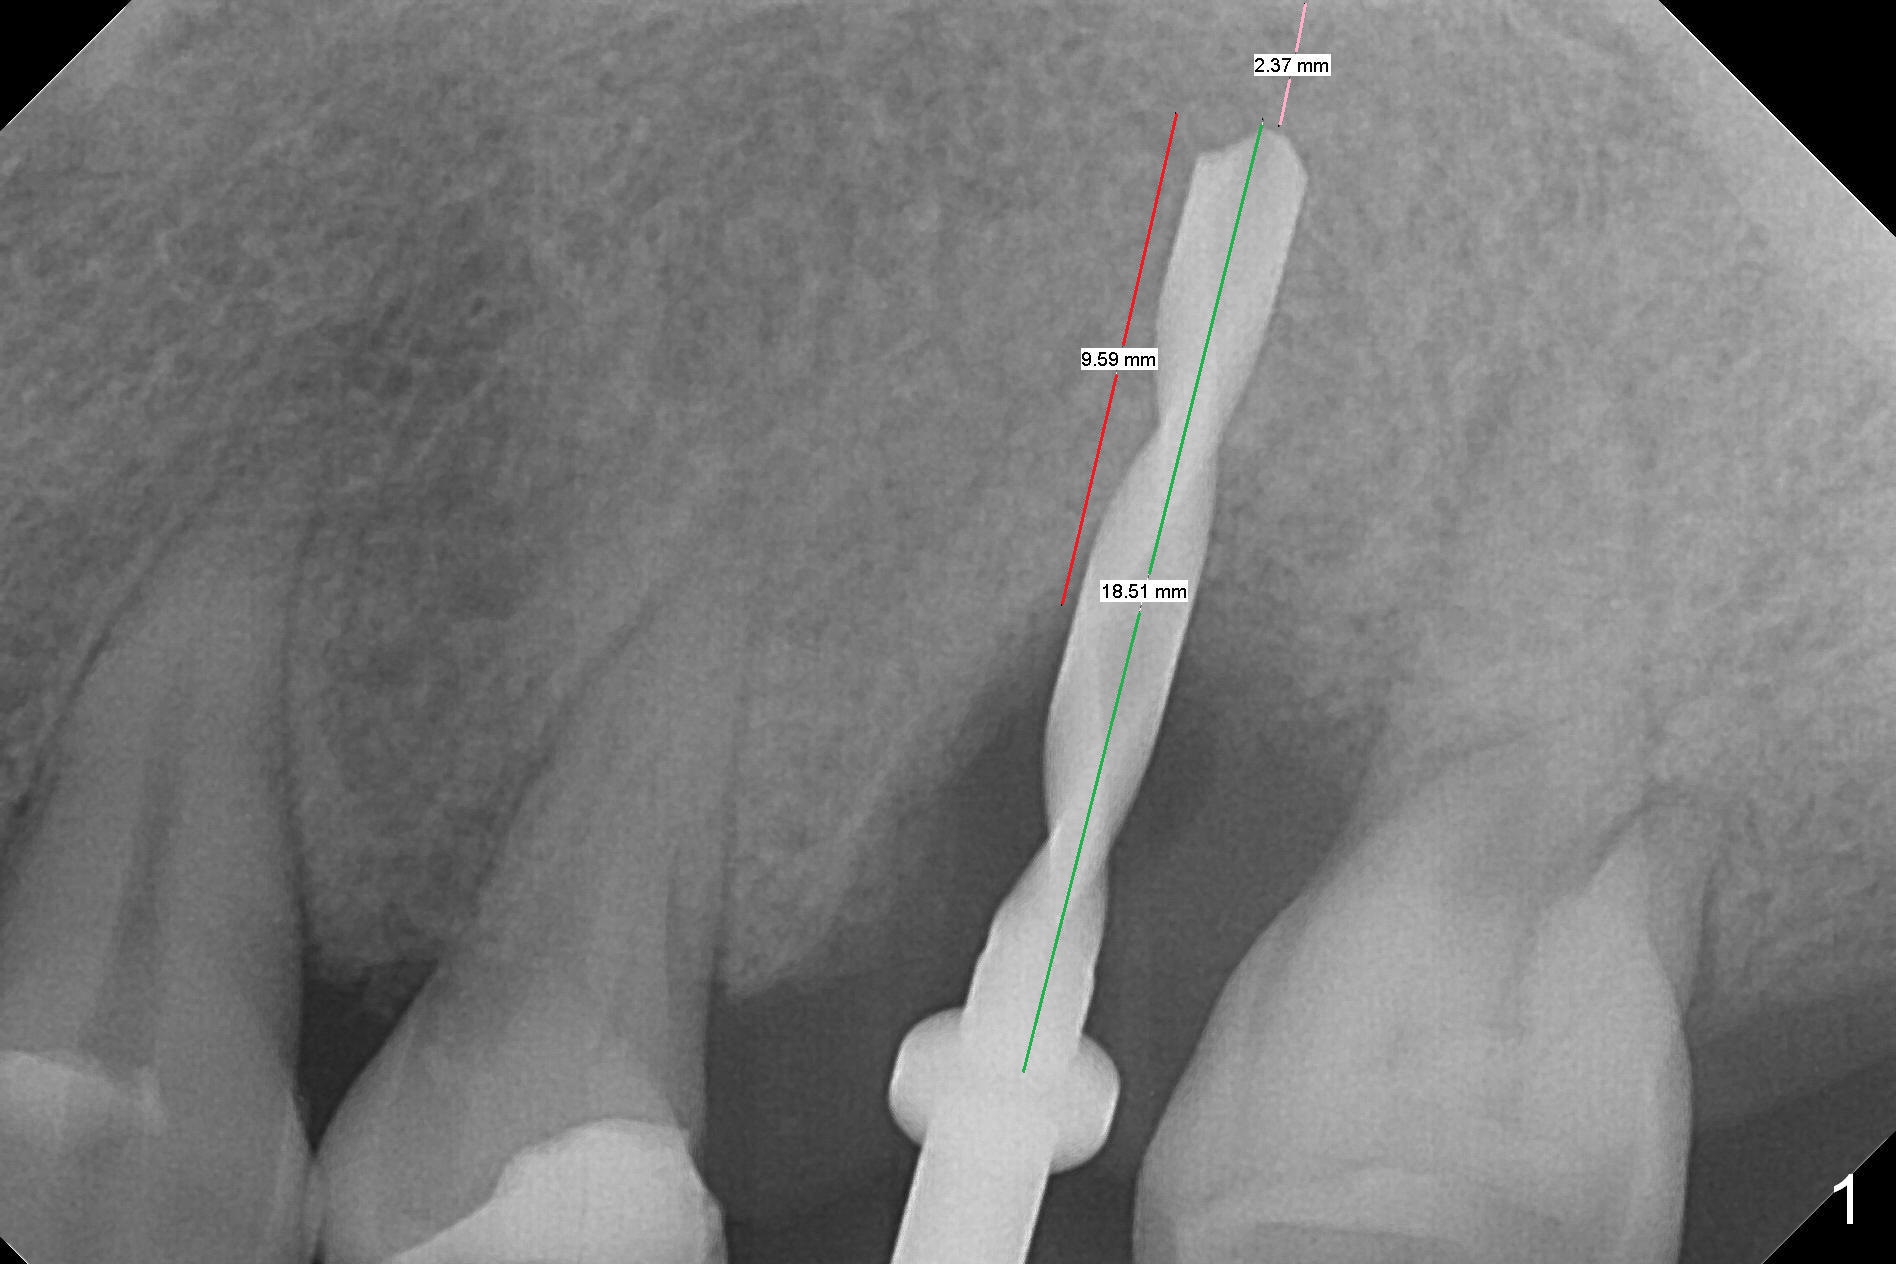

Initial osteotomy depth is 18 mm (Fig.1 green line) with 9 mm in the native bone (red line). The bone density feels to be low. There is at least 2 more mm bone apically (pink line). The depth is increased by 2 mm so that when a 3.8x15 mm implant is placed, there is 10-11 mm implant/bone contact (Fig.2 red line). There is large bony defect (Fig.3 *), which is bone grafted (Fig.4 *). Finally a longer abutment is placed (4.5x5.5(5) in Fig.4 vs. 4.5x4(5) in Fig.2,3). The 5 mm cuff does not look too long buccally (Fig.5) or palatally (Fig.6). To prevent postop buccal gingival overgrowth (2), the buccal margin of an immediate provisional is subgingival (Fig.7-9 *). Bone density between #13 and 14 appears to increase 3 months postop (Fig.10). The implant seems to be equi-crestal (Fig.11 ^). There seems to be more bone growth (i.e., decreasing gap) 6 months postop (Fig.12). Impression is taken. A crown is delivered nearly 7 months postop (08/07/2017). While there is minimal bone loss at #13 and 15 three years and 4 months post cementation, the tooth #14 and 18 are mobile (Fig.13,14).